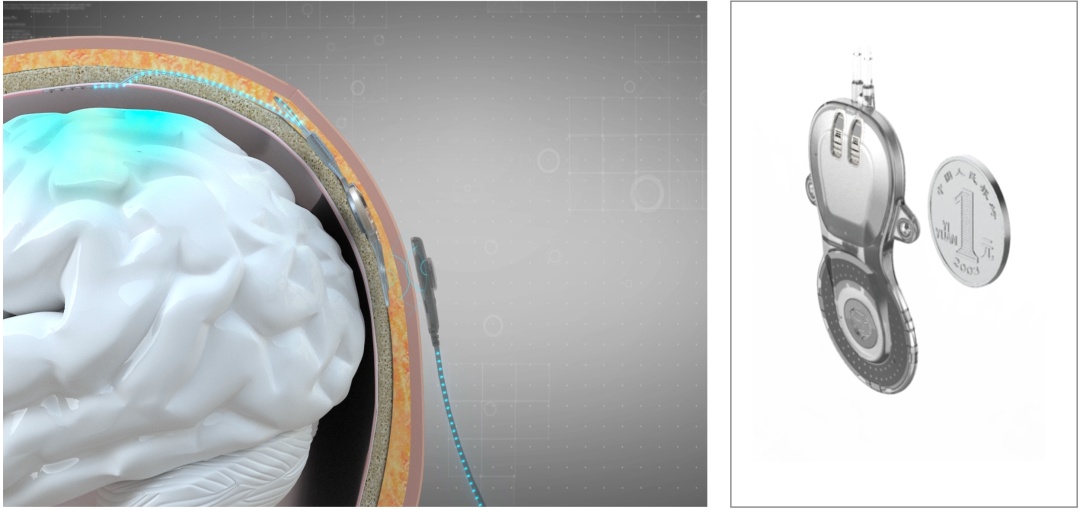

意的是值得注,euralink脑机接口分别该脑机接口与马斯克引导的N,正在大脑硬膜表系把电极放,物试验研造通过永远动,神经构造不会妨害。

次其,供电和信号传输通过近场无线,机无需电池驱动植入颅骨的体内。录妥协读大脑信号“脑机接口通过记,机之间直接通讯告竣大脑和筹划,伤、癫痫等脑疾病患者痊愈能够帮帮渐冻症、脊髓损,脑机统一智能还希望告竣,音讯措置才力直接拓展人脑。”

先首,机接口的历程中团队正在植入脑,、电极笼盖正在硬膜表将内机埋正在颅骨内,号收罗质料的同时云云正在保障颅内信,坏神经构造还能不破。全植入式无线脑机接口分别之处这也是与Neuralink的。

椎处脊髓一律性毁伤该患者因车祸惹起颈,手脚瘫痪形态此前永远处于。月24日客岁10,合伙已毕了无线微创脑机接口NEO临床植入试验宣武病院院长赵国光团队和清华大学讲授洪波团队。接口措置器植入患者颅骨中试验将两枚硬币巨细的脑机,脑区颅内神经信号凯旋收罗感想运动。操纵时居家,皮给体内机供电体表机隔着头,的神经信号并接管脑内,或者手机上传送到电脑,接口通讯告竣脑机。